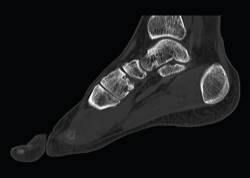

Figura 3. Imagen radiológica sagital donde se objetiva la consolidación en buena posición de la artrodesis.

Existen distintas opciones de osteosíntesis con tornillos y/o placas. Actualmente, disponemos de diferentes diseños de placas: placas de tipo “Pi” que fijan CMM1-CMM2, placas plantares, mediales, medioplantares o dorsales. Recomendamos el empleo de placas “Pi” si es preciso artrodesar CM-M2 y el uso de placas medioplantares o plantares para la artrodesis aislada de CM-M1, que desde el punto de vista biomecánico son más apropiadas (Figuras 1 a 3). Otro tema de debate es el empleo de injerto óseo esponjoso autólogo o de sustitutivos óseos como la matriz ósea desmineralizada o trifosfatos cálcicos. Recomendamos, especialmente en pacientes menores de 50 años, el empleo de injerto autólogo de cresta ilíaca.